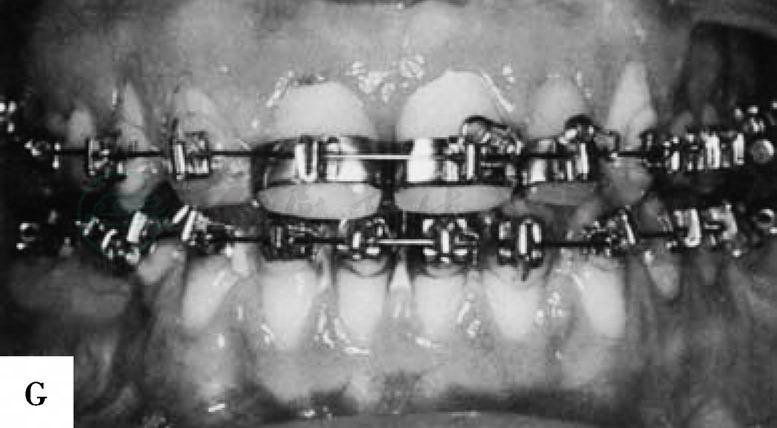

完成截骨并去除部分骨质后,将下颌的近心骨段和远心骨段进入到预制的板中并行颌间结扎固定。如果垂直截骨部位的软组织阻碍下颌远心骨段的后退可予部分切除,切除的软组织的宽度应小于下颌远心骨段后退的距离使骨组织后退后软组织能保持接触,利于术后缝合此处软组织伤口。可于下颌骨下缘处行骨间钢丝结扎固定,如果采用坚固固定方法可以用直的四孔接骨板配合以单皮质螺钉进行固定,需在下颌管上、下方各固定一个接骨板。坚固固定后可以将骨间结扎的钢丝去除,在缝合软组织切口前应检查骨段间稳定性和骨段位置。冲洗术野后用可吸收缝线缝合关闭软组织伤口。如果应用颌间固定方法进行固定,其术后应保持6~8周(图2)。

图2 下颌前突畸形患者,采用下颌体部台阶状截骨术进行矫正。A-D,患者术前面像和颌骨X线片。